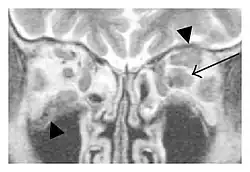

| Mass lesion around the right optic disc in a 44-year-old man with IgG4-related ophthalmic disease and a serum IgG4 of 599 mg/dL.[1] (T2-weighted MRI) | |

The extent of inflammation that can occur in IgG4-ROD is well demonstrated on magnetic resonance imaging (MRI).

Infraorbital nerve enlargement (IONE) is considered to be a particularly suspicious sign of IgG4-ROD, but seems to occur only when inflammation is in direct contact with the infraorbital canal.[10] IONE is defined as the infraorbital nerve diameter being greater than the optic nerve diameter in the coronal plane.